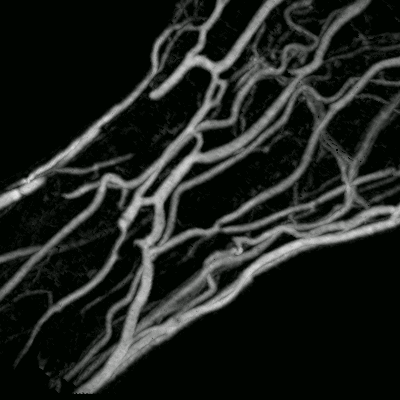

MIP using a cell array and direction dependent preprocessing for 12 clusters of viewing directions. The tolerance threshold for noise compensation has been set to 0%. 31% of all cells removed.

The same data preprocessed with a tolerance threshold  of 1%. No difference noticeable in the images. 81% of all cells removed.

The same data preprocessed with a tolerance threshold  of 2%. Slight differences appear mainly in low-gradient areas containing less relevant information.. 93% of all cells removed.